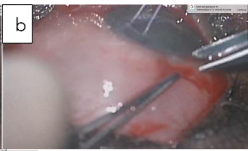

Combined GDD and phacoemulsification. The first stage is as described above but the insertion of the tube into the anterior chamber and closure of the conjunctiva were done after the phacoemulsification. The second stage is a standard phacoemulsification with the intraocular lens inserted into the capsular bag using the divide and conquers technique.